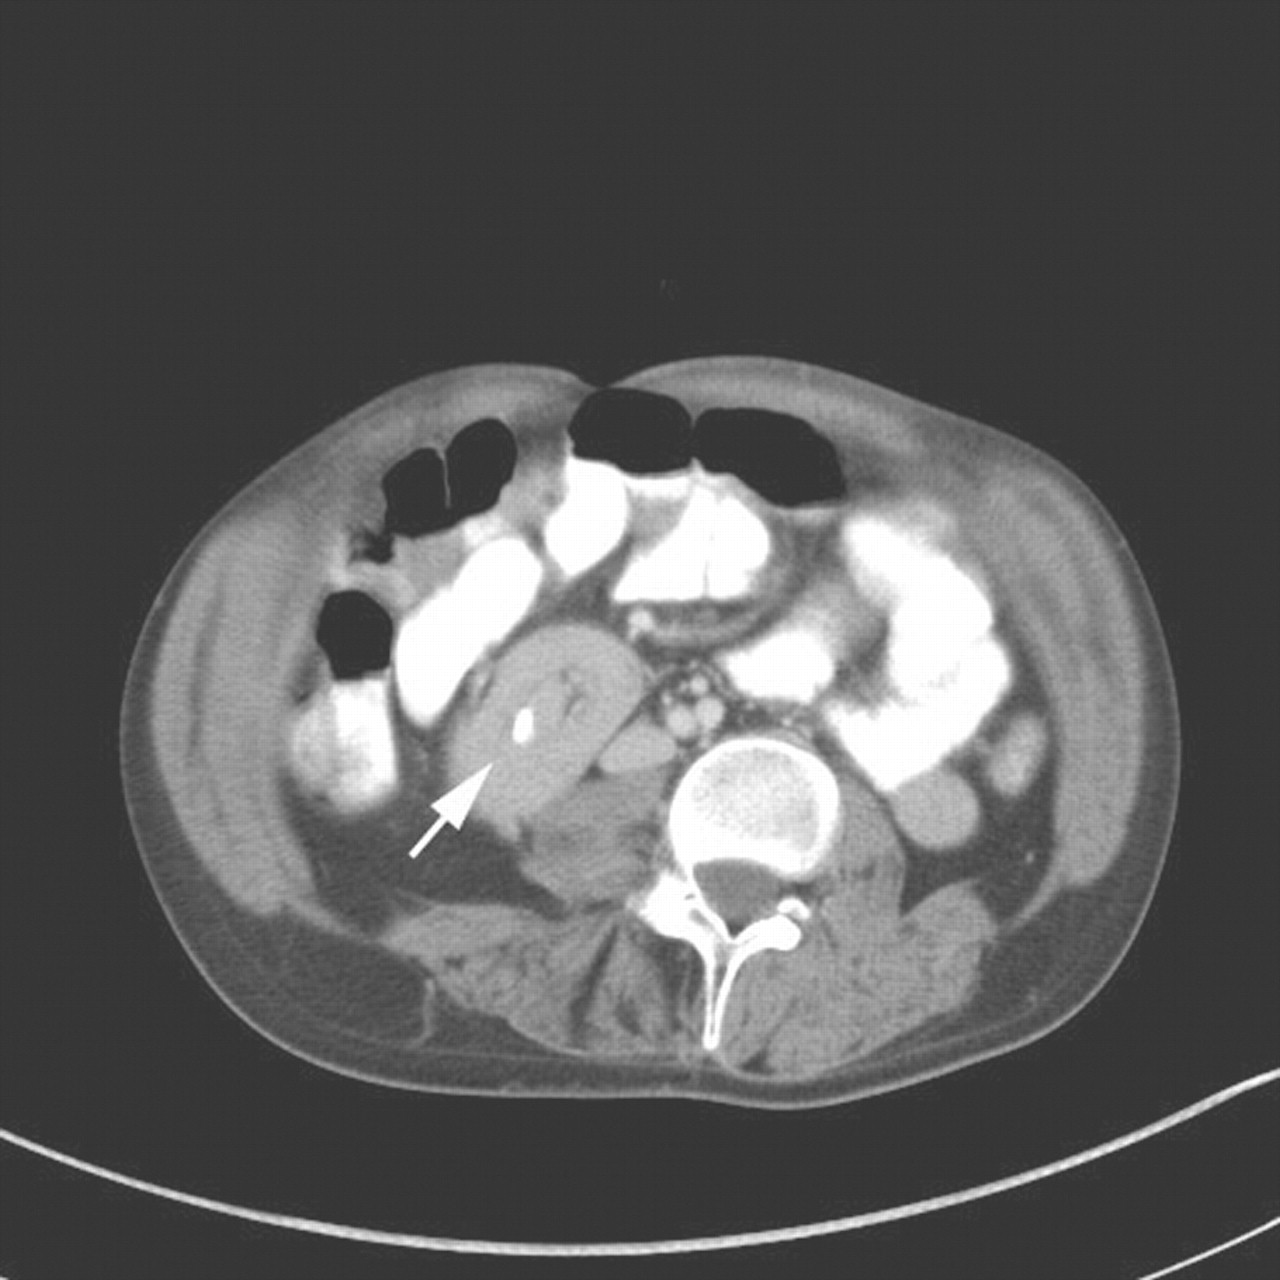

Identifying small bowel intussusception related to a gastroenteric Feeding Tube In Small Bowel Feeding can commence when position of the feeding tube is confirmed in the small bowel. A peg is a feeding tube that is placed into your stomach (see figure 1, left). Tube feeding (enteral nutrition) delivers liquid nutrition through a flexible tube that goes in through your nose or directly into your stomach or small. This opening is called a. Feeding Tube In Small Bowel.